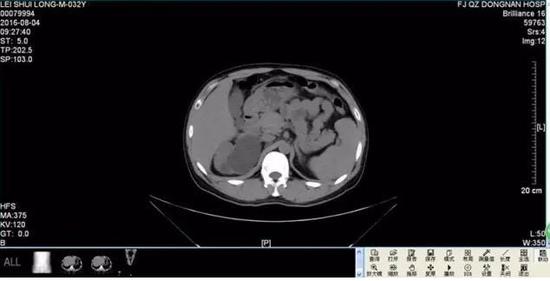

几天后,雷先生来到医院做进一步检查,令雷先生和医生们吃惊的是,腹腔巨大囊肿其实是右侧重复肾输尿管肿大,最大直径竟有13厘米,而正常人的输尿管只有0.8厘米粗,最终,雷先生被确诊患有罕见的巨输尿管症,医院根据雷先生的情况对其右侧重复肾上半肾、重复输尿管进行了切除,术后恢复良好。